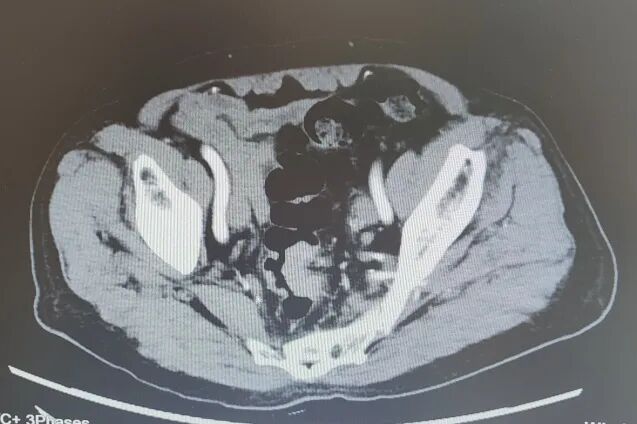

内容提要 近日,葫芦岛市第二人民医院胃肠外科乔世峰教授团队凭借过硬的微创诊疗技术与一站式全程服务,成功为一名八旬高龄晚期直肠恶性肿瘤患者实施根治手术,用专业实力打破异地就医困局,收获了患者及家属百分百的信任与认可。 Part.01 一条出诊信息,明确就诊方向 李大爷年近八旬,便血症状持续5个月,起初并未引起足够重视。直到肠镜检查结果出来,家人才意识到病情的严重性:肿瘤已环绕肠腔三分之二,病理为腺癌,治疗刻不容缓。 🔺入院时患者肠镜(左)及影像照片(右) 考虑到老人年事已高,家属多方打听,希望能找到此领域的权威专家为老人手术。几经辗转,他们认定了辽西地区胃肠外科权威专家——锦州附属医院胃肠外科乔世峰主任。正当家属做好带着老人奔赴外地手术的准备时,一条消息让他们欣喜若狂:乔世峰主任已全职加盟葫芦岛市第二人民医院,于是当即带着检查报告前来就诊。 Part.02 微创精准施治 小切口解决大问题 结合患者肿瘤情况及高龄身体基础,乔世峰主任、张凯副主任带领团队为患者量身制定了腹腔镜微创根治手术方案。相较于传统开腹手术,腹腔镜微创手术具有创伤小、出血少、恢复快的显著优势。对于高龄中晚期肿瘤患者而言,该术式既能实现肿瘤的彻底切除与区域淋巴结清扫,又能最大程度保护肠道正常功能,减少术后并发症,为后续康复与辅助治疗奠定坚实基础。 术中,团队借助腹腔镜高清视野,顺利完成肿瘤切除、淋巴结清扫及肠道吻合,最大限度保留了正常组织。整台手术出血量仅10毫升,真正实现了“小切口解决大问题”。 Part.03 一站式诊疗暖人心 优质服务获盛赞 手术成功是治疗的第一步,规范的术后辅助治疗关乎患者长期预后。术后,科室迅速联合肿瘤内科开展多学科会诊,依据病理及免疫组化结果,为患者量身制定化疗方案,实现“手术+化疗+康复”一站式全程诊疗服务,让患者少奔波、更安心,有效降低复发风险,提升治愈希望。 “原本已经做好去外地手术的准备,没想到乔主任就在家门口。手术做得好,后续治疗也安排得明明白白,我们全家都特别放心。”李大爷的家属由衷感谢道。 Part.04 深耕胃肠肿瘤近40年 顶级专家坐阵“家门口” 乔世峰教授深耕胃肠肿瘤规范化治疗与疑难病例诊治近40年,是省内较早开展腹腔镜胃肠肿瘤微创手术的权威专家,在辽西地区享有盛誉。此次全职加盟,将有力推动市二院胃肠外科诊疗水平提质升级,更好满足群众的就医需求。如今,患者无需远赴外地奔波求医,在家门口就能享受到高水平、精准化的优质诊疗服务。葫芦岛市第二人民医院胃肠外科以实际行动践行“大病不出市”的承诺,让更多患者在家门口就能看得好病、安心康复。 Part.05 人民医院 人民名医 乔世峰 博士后 主任医师 教授 硕士研究生导师 ·葫芦岛市第二人民医院胃肠外科主任 ·原锦州医科大学附属第一医院胃肠外科主任 ·首都医科大学医学博士、天津医科大学博士后 ·辽宁省医学会外科分会疝与腹壁外科学组委员 ·辽宁省医学会肠外肠内营养学会委员 ·东北三省肠外肠内营养支持专业委员会委员 ·辽宁省中西医结合学会肿瘤专业委员会常委 ·《中国肿瘤生物治疗杂志》特约审稿专家 专业特色:省内胃肠外科领域领军专家,从事普外科工作近40年,擅长胃肠道多发、疑难病诊治,精通普外科各类手术,如胃癌、结肠癌、疝、肠梗阻、肝癌、胆囊切除术、胰腺手术等。深耕胃肠道肿瘤规范化治疗与微创技术创新,在省内较早开展腹腔镜微创胃肠肿瘤手术,具有极高造诣。在国家核心期刊发表学术论文20余篇,SCI论文10余篇。 张凯 副主任医师 硕士研究生 ·葫芦岛市第二人民医院胃肠外科副主任 ·辽宁省生命科学学会胃肠肿瘤专业委员会委员 ·中医临床药学分会委员理事 ·沈阳市抗癌协胃癌专业委员会委员 专业特色:以腹部外科为诊治方向,擅长普通外科多发及疑难病的诊断、治疗和手术。以微创技术为特色优势,擅长腹腔镜阑尾切除术、腹股沟疝修补术、结直肠癌根治术、胃癌根治术。先后发表论文2篇,完成“腹腔镜、胆道镜及两镜联合手术临床应用”科研项目,并获得了葫芦岛市科学技术成果奖励二等奖,学术论文类获得葫芦岛市自然科学学术成果一等奖。